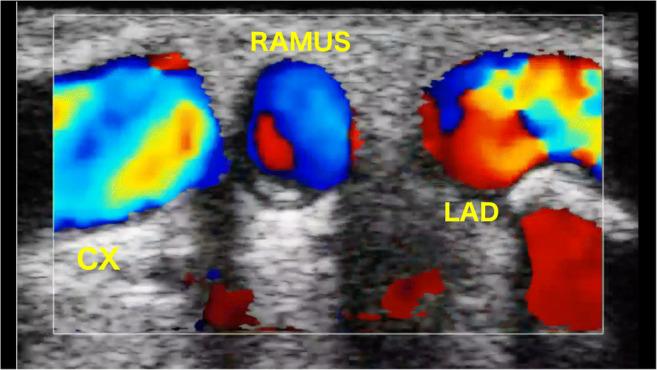

The left main can be scanned in longitudinal and cross section views. Scrolling the probe distally in short axis view at the level of the bifurcation, the LAD will be on the right and the LCx on the left. If there is a ramus intermedius, it will appear between the LAD and LCx (Fig. 2).

Fig. 2.

Trifurcation of the left main stem. Short axis view

With the use of 2-D and color flow mapping (CFM), imaging the extent of plaque, lumen reduction, and flow acceleration can be easily assessed. Moreover, there is the chance to measure the diameter of the residual lumen calculating the percentage of stenosis. To avoid over or underestimation of the stenosis, it is important to not compress the vessel below the probe.